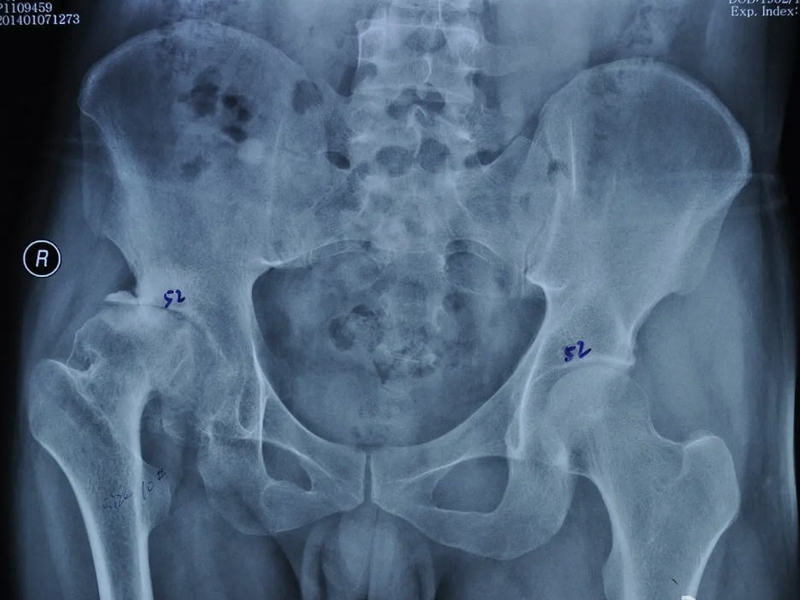

兒童髖關(guān)節(jié)積液,可能有后遺癥喲。

兒童感冒發(fā)燒拉肚子,都可能引起髖關(guān)節(jié)積液。因?yàn)楹⒆映3Uf同側(cè)膝蓋疼痛,就更容易漏診。如果核磁發(fā)現(xiàn)的早,一般經(jīng)過適當(dāng)治療,積液就消失了,大部分兒童也不會留下后遺癥。但是如果治療不及時積液反復(fù)發(fā)作,就會因?yàn)殛P(guān)節(jié)囊膨脹導(dǎo)致股骨頭外移,嚴(yán)重的甚至脫位。股骨頭外移,股骨頭和髖臼窩承重位置改變,對股骨頭生長板力學(xué)刺激改變就會引起形狀改變。比如股骨頭變扁變大,臼窩變淺變寬。就像下面的圖一樣。嚴(yán)重的成為扁平髖,輕度的可能成為髖發(fā)育不良。當(dāng)然髖發(fā)育不良還有遺傳等因素。

中山大學(xué)附屬第八醫(yī)院運(yùn)動醫(yī)學(xué)科科普號2023年12月24日261